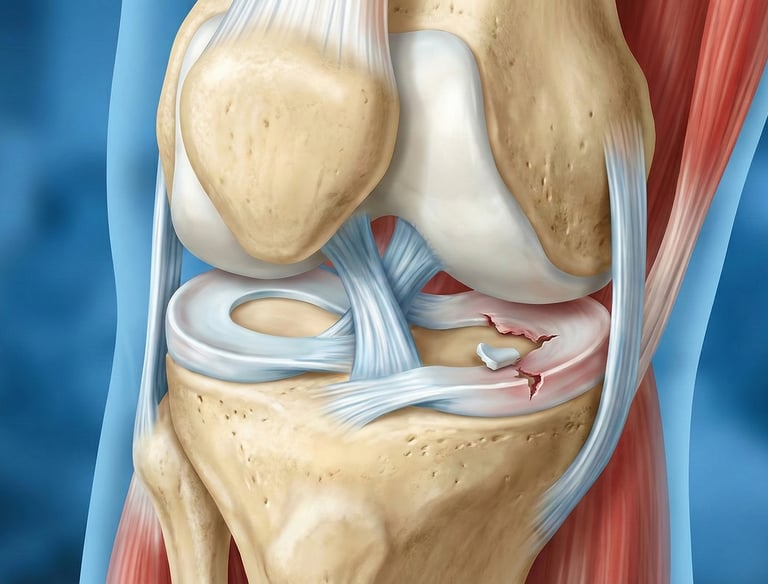

Kova Sapı Menisküs Yırtığı — Nedir?

Menisküsün uzunlamasına yırtılarak orta kısma (eklem içine) yer değiştirmesidir. Adını, yer değiştiren parçanın kova sapı formunu andırmasından alır.

Kimlerde Görülür?

Genellikle genç sporcularda, ani dönme/bükülme travmaları sonucunda oluşur.

Menisküs yaralanmalarının ortalama %10 u 'Kova Sapı Yırtığı' olarak tarif edilen türdendir. Özellikle genellikle genç, sporcularda torsiyon (diz dönmesi) hareketiyle orataya çıkan ağrı, şişlik (efüzyon-sıvı toplanması) ve eklem kilitlenmesi ile karakterize bir klinik tablodur.